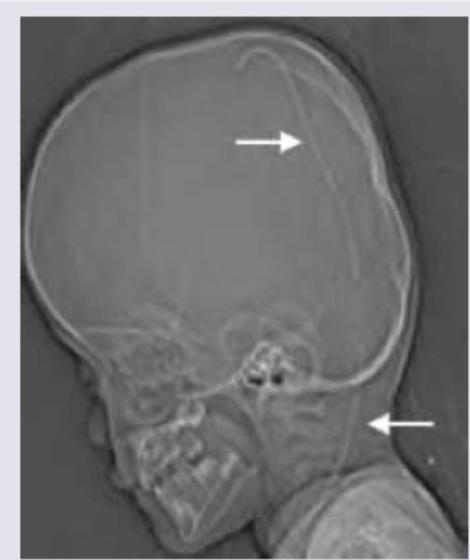

Explanation: ***Ventriculoperitoneal shunt*** - The image clearly shows a **thin, radiopaque tube** extending from the cranial vault (indicated by the top arrow) down through the neck (indicated by the bottom arrow), consistent with the path of a ventriculoperitoneal shunt. - A ventriculoperitoneal shunt is surgically placed to **drain excess cerebrospinal fluid** from the brain's ventricles to the peritoneal cavity, commonly used in cases of hydrocephalus. *Enlarged sella turcica* - An enlarged sella turcica would appear as an expanded bony structure housing the pituitary gland, which is **not visible** or indicated in this image. - This finding is usually associated with **pituitary tumors** or other conditions causing increased intracranial pressure, but not identifiable here. *Craniosynostosis* - Craniosynostosis involves the **premature fusion of cranial sutures**, leading to an abnormally shaped skull. - While it can cause abnormal skull contour, there are **no clear signs of fused sutures** or specific deformation indicative of craniosynostosis in this lateral skull radiograph. *Pneumocephalus* - Pneumocephalus refers to the presence of **air within the cranial cavity**. - This would appear as **radiolucent (dark) areas** within the skull, which are not observed in the image; instead, a radiopaque structure is clearly visible.